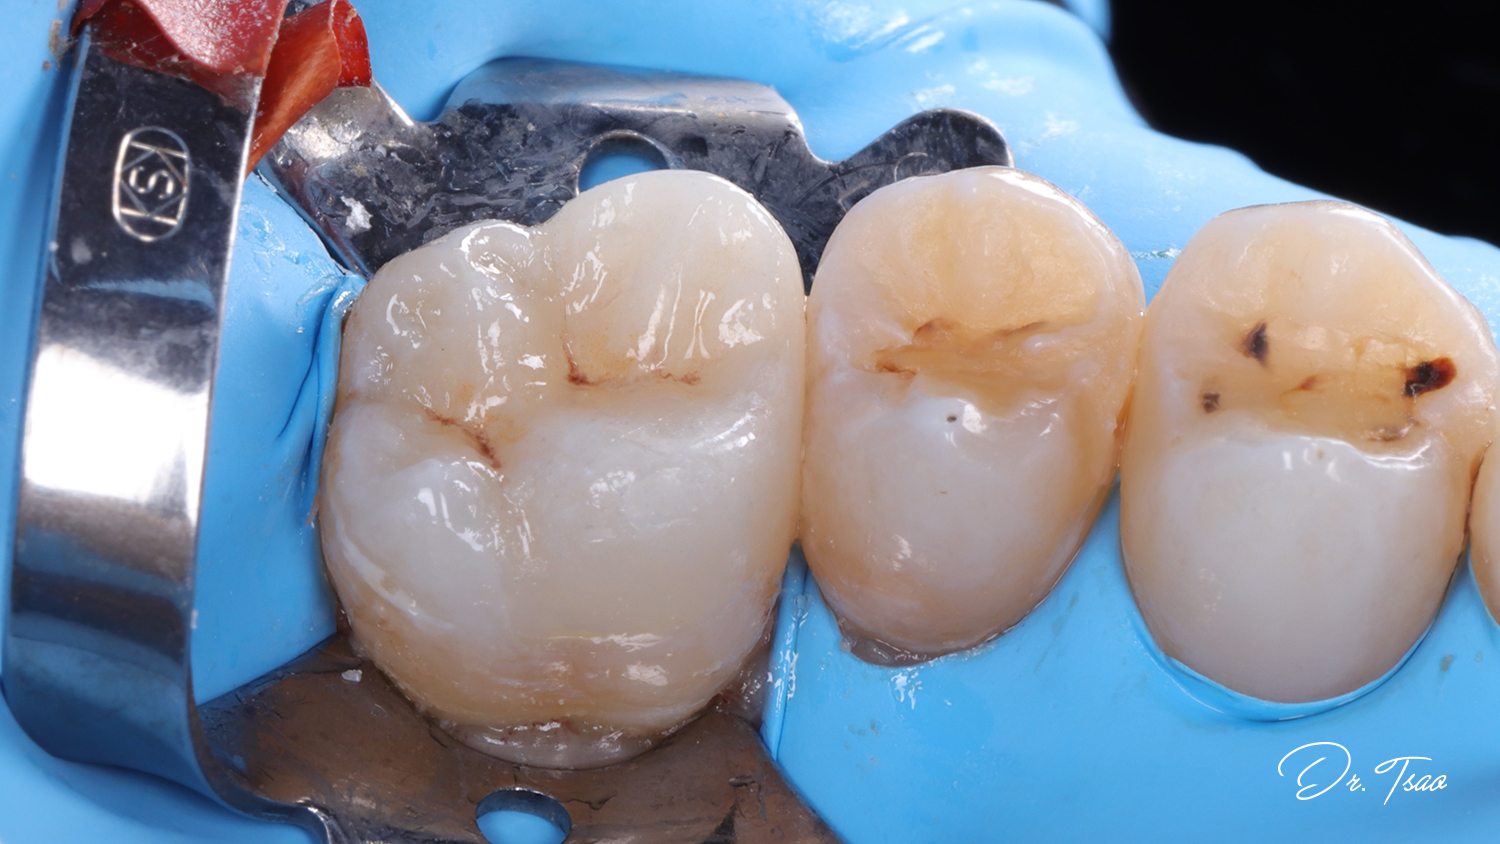

嵌體的修磨大概是牙科治療中最有趣的了.

不僅要想怎麼樣對受力比較理想,

還要兼顧最少量的修磨.

而且臨床上的遭遇有千百種, 每一個都是量身訂做,

也正因如此, 每個案例都是獨一無二的存在.